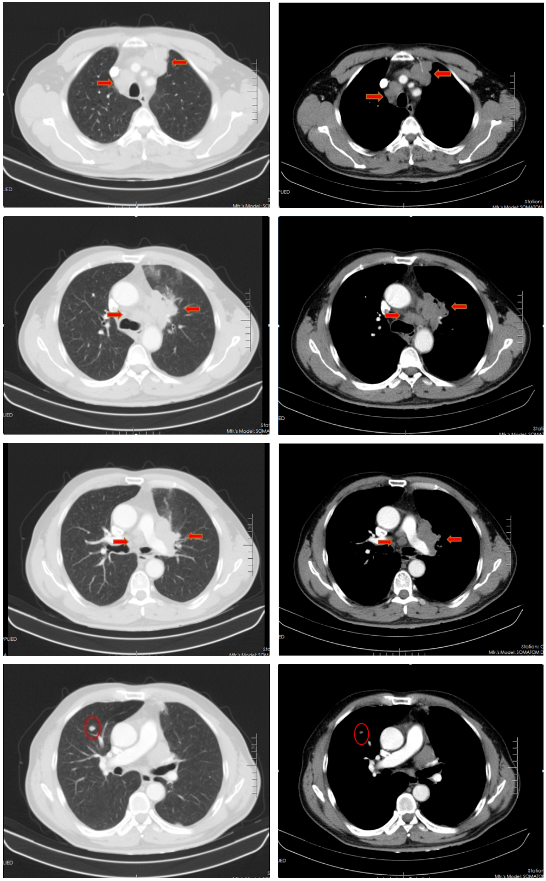

胸部增强CT(2022-02-12):左肺门及纵隔内见团块状软组织密度影,大小约62mm×42mm,边界不规整,内见血管影穿行,增强扫描呈轻度强化,局部支气管狭窄,远端肺内见片状磨玻璃密度影,边界欠清。右肺上叶见结节状密度增高影,较大直径约为8mm,增强扫描呈轻中度强化,右侧斜裂见长径约为6mm的高密度影,增强扫描未见明显强化;两肺透亮度增强,左肺下叶胸膜下囊状透光区。余气管、支气管通畅,未见明显狭窄、阻塞。纵隔和左肺门区见多发肿大淋巴结影,部分融合。两侧胸腔无明显积液。胸部CT诊断:左肺门及纵隔内占位,考虑肺Ca;纵隔及左肺门淋巴结肿大;右肺上叶结节,转移可能;右侧斜裂下结节;两肺肺气肿、左肺下叶肺大泡。

胸部CT(2022-04-12):左肺门及纵隔内见团块状软组织密度影,大小约57mm×37mm,边界不规整,局部支气管狭窄,远端肺内见片状磨玻璃密度影,边界欠清。右肺上叶见结节状密度增高影,较大直径约为9mm,右侧斜裂见长径约为7mm的高密度影;两肺透亮度增强,左肺下叶胸膜下囊状透光区;两肺可见索条状影。余气管、支气管通畅,未见明显狭窄、阻塞。纵隔和左肺门区见多发肿大淋巴结影,部分融合。两侧胸腔无明显积液。胸部CT诊断:左肺占位复查;纵隔及左肺门淋巴结肿大;右肺上叶结节,转移可能;右侧斜裂下结节;两肺肺气肿、左肺下叶肺大泡。

胸部CT(2022-07-15):双侧肺野透亮度增加,以两上肺和胸膜下明显。双肺纹理增多、增粗,紊乱,左肺上叶条片状高密度灶,大小约45mm×19mm,小叶间隔增厚。气管、左右主支气管无明显狭窄。纵隔内未见肿大淋巴结影。两侧胸腔无明显积液。胸部CT诊断:左上肺门占位复查;慢性支气管炎-肺气肿样改变。

治疗后评价:患者经过EP方案联合斯鲁利单抗治疗四周期后,患者咳嗽、咳痰及左侧胸痛症状消失,体重逐渐恢复;影像学提示左肺病灶及纵膈淋巴结及肺门淋巴结较前明显缩小(缩小>30%),右肺结节基本消失;疗效评价:PR(接近CR)。

胸部CT(2022-08-30):双侧肺野透亮度增加,以两上肺和胸膜下明显。双肺纹理增多、增粗,紊乱,左肺上叶见条片状高密度灶,大小29mm×18mm,小叶间隔增厚,两肺下叶见囊状透亮区。气管、左右主支气管无明显狭窄。纵隔内未见肿大淋巴结影。两侧胸腔无明显积液。胸部CT诊断:左上肺门占位复查;慢性支气管炎-肺气肿样改变;两肺下叶肺气肿。

治疗后评价:患者经过斯鲁利单抗单药维持治疗两周期后,患者未再出现咳嗽等症状,体重逐渐增加。影像学提示左肺病灶及纵隔淋巴结及肺门淋巴结、右肺结节基本消失,疗效评价接近CR。

病例小结

该患者为ⅣB期小细胞肺癌,一线采用标准化疗方案(EP)治疗2周期后疗效评估:SD,患者化疗敏感性不高;第二阶段治疗根据2022年CSCO小细胞肺癌诊疗指南,患者采用斯鲁利单抗联合EP方案,治疗2周期后体力状况明显改善,4周期后疗效评估:PR;第三阶段采用斯鲁利单抗单药维持治疗,2周期后影像学评估,左肺病灶及纵膈淋巴结及肺门淋巴结、右肺结节基本消失,疗效评估:接近CR。